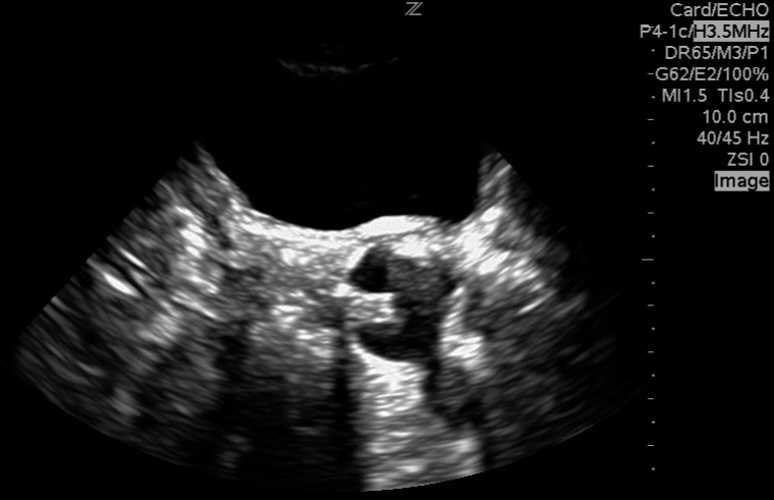

Equipment

- Transducer: Curvilinear Ultrasound Probe or Phased Array Transducer (5-3.5 MHz)

- Preset: Abdominal or Renal